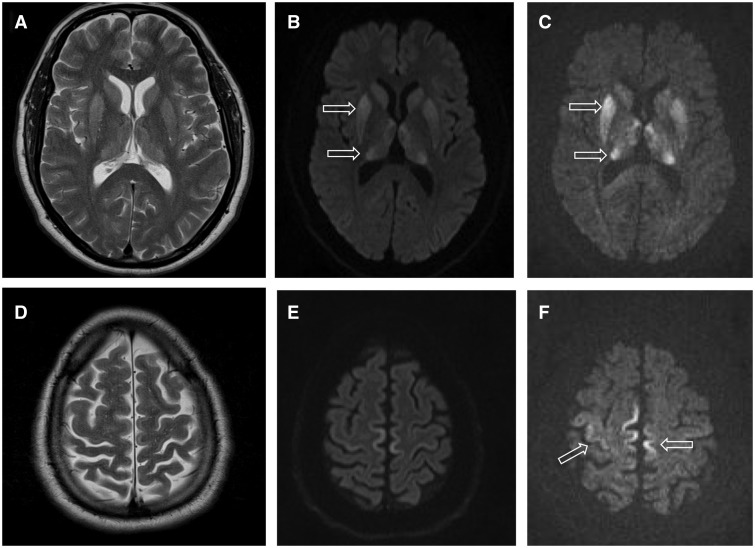

RPI Deficiency manifests as progressive leukoencephalopathy (white matter disease in the brain), developmental delays, seizures, and eventual optic atrophy leading to vision loss. The extreme rarity of this condition has hampered research efforts, and there is currently no effective treatment. Management focuses on supportive care and symptom control.